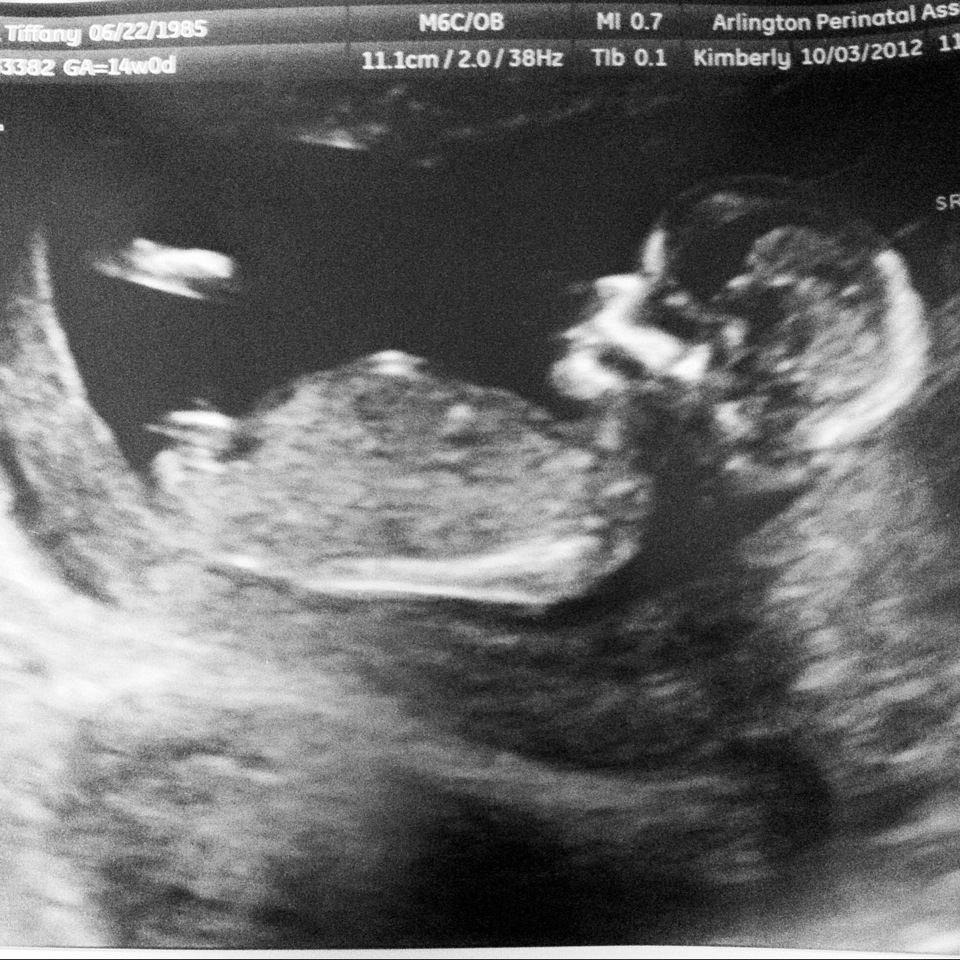

Guessing girl

Girl!!

Def a girl!

Girl :)

Maybe boy if that is the nub behind the leg??

What a nub shot! i think girl :)

Girl

yep girl from me to